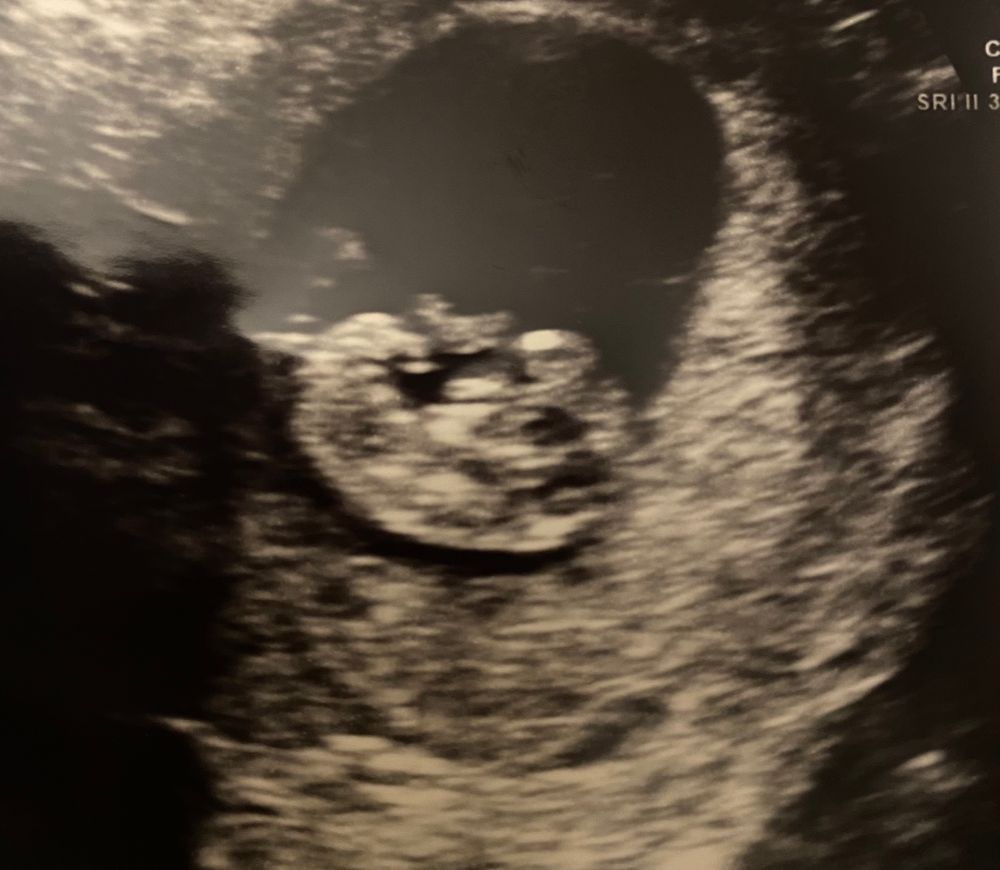

Девочки, пришла домой после узи и истерика. Срок 10 недель 1 день, пя размер 31,7, а эмбрион 30,1((( ручками машет, ножками.. свернулся в углу как креветка, ему тесно. Узистка ещё в прошлый раз сказала, пя маловато, но он было больше крошки в 3 раза. Сердечко 158 ударов, тоже не много. Я так плачу от бессилия, что ничем не могу помочь, пытаюсь успокоиться и снова накатывает. Выпила витамины, актовегин хочу что то сделать для малыша и не знаю что 🥺

MissKanaverel, по фото у вас все нормально, вон сколько у него места, просто ему нравится в уголочке сидеть.

Дочка в 10,2 нед, СВД - 35 мм, КТР -34 мм. Лежит вот рядышком, нервы треплет)